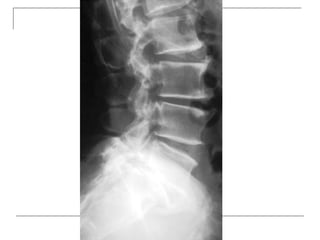

Plain radiograph

   AP

-loss of lumbar lordosis

-reduced disc space

-osteophytes

-deformity

-fracture (increase interpedicular distance)

-osteoporosis

-pedicle disruption

   Lateral

-fracture/wedging

-kyphosis

-spondylolisthesis

   Oblique

-spondylolysis (SCOTTIE DOG)

Plain x-rays

Plain radiograph  AP -loss of lumbar lordosis -reduced disc space -osteophytes -deformity -fracture (increase interpedicular distance) -osteoporosis -pedicle disruption

Lateral -fracture/wedging -kyphosis -spondylolisthesis  Oblique -spondylolysis (SCOTTIE DOG)